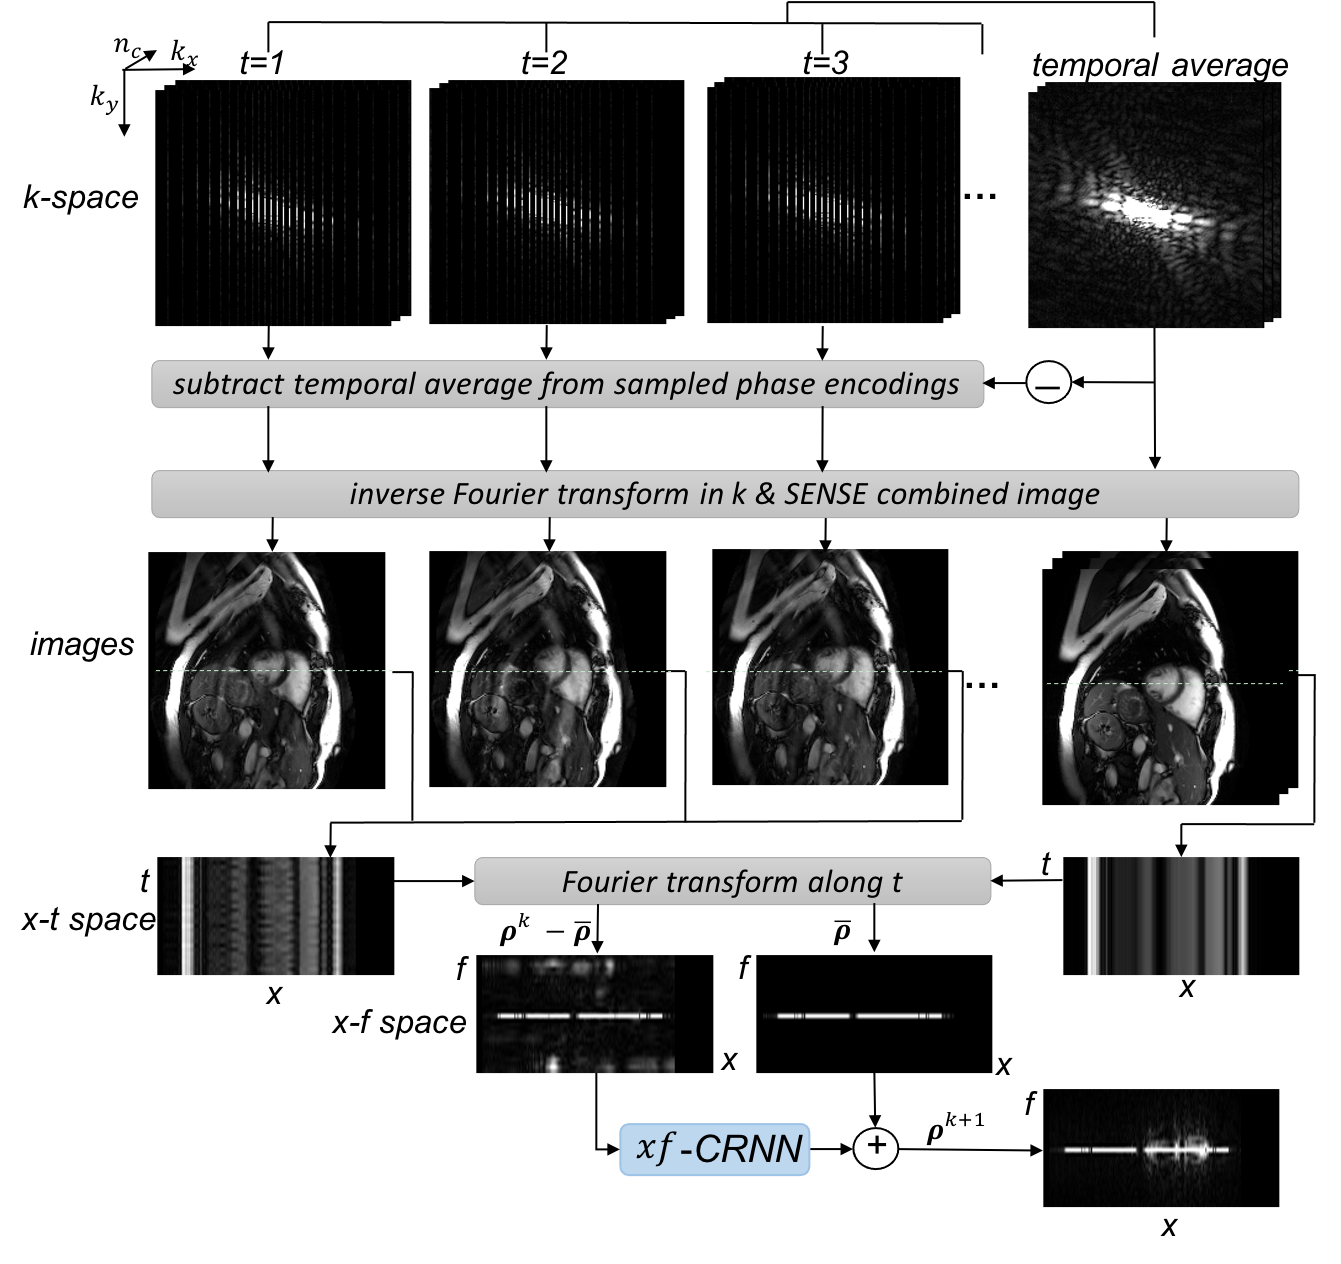

Based on the model formulation in Eq. 5, we propose to embed the iterative reconstruction process into a DL framework to further improve the reconstruction quality with faster reconstruction speed and higher acceleration rates. Specifically, we propose a complementary time-frequency domain network (CTFNet) for the dynamic parallel MRI reconstruction to exploit the spatio-temporal correlations in complementary spatio-temporal and temporal frequency domains. Our model consists of four core components: (1) an -CRNN to implicitly learn the regularisation from the training data itself and perform the iterative de-aliasing in - domain, corresponding to Eq. 5a; (2) an -CRNN similarly as the learning-based proximal operator in the spatio-temporal image domain, corresponding to Eq. 5b; (3) a pDC layer that performs coil-wise DC in PI (Eq. 5c); and (4) a wCP layer that is naturally derived from Eq. 5d and performs the weighted coupling. An illustrative diagram of the proposed model is shown in Fig. 1. Note that the iterative reconstruction process as stated in Eq. 5 is modelled via the convolutional recurrent neural networks (CRNN) with recurrence over iterations. Details of each component of our network is explained hereafter.

The illustrative diagram of - reconstruction is shown in Fig. 2. Specifically, we formulate the - to - transformation process in PI as an - transform layer in the network. The - transform layer receives input from multi-coil - space data, and then transform it to - space as inputs to -CRNN. Details of the process are illustrated and explained in Fig. 2. Note that the value range of the direct current component of the undersampled data in x-f space is lower than that of the temporal average, therefore after subtraction, the direct current component still remains but with a different value range from the temporal average. This also means that the subtracted data in image space can look similar to the temporal average but with a lower intensity range and aliasing artefacts. After the signal de-aliasing in - domain, another inverse Fourier transform along is adopted to transform the estimated - signal back to dynamic image space for the subsequent weighted coupling with other predictions, as shown in Fig. 1.

The detailed network architecture of the proposed CTFNet is shown in Fig. 1. The CTFNet architecture consists of four components, where each component is corresponding to each subequation in Eq. 11, respectively. In detail, -CRNN is composed of 4 layers of CRNN-i and 1 layer of 2D CNN with a residual connection from the baseline estimate. The 2D convolutions are applied over the and dimensions, and the dimension is viewed as the batch dimension. For the -CRNN model, a variation of architecture [29] is employed which consists of 4 layers of BCRNN evolving over both temporal and iteration dimensions, 1 layer of 2D CNN and a residual connection. Here the 2D convolutions are applied on the spatial dimensions with recurrence over time dimension in BCRNN, whereas in 2D CNN layer the time dimension is viewed as the batch dimension. We used dilated 2D convolutions with kernel size and dilation factor to increase of the receptive field sizes. The number of input and output channels of the network was 2, representing the real and imaginary part of the complex-valued data.